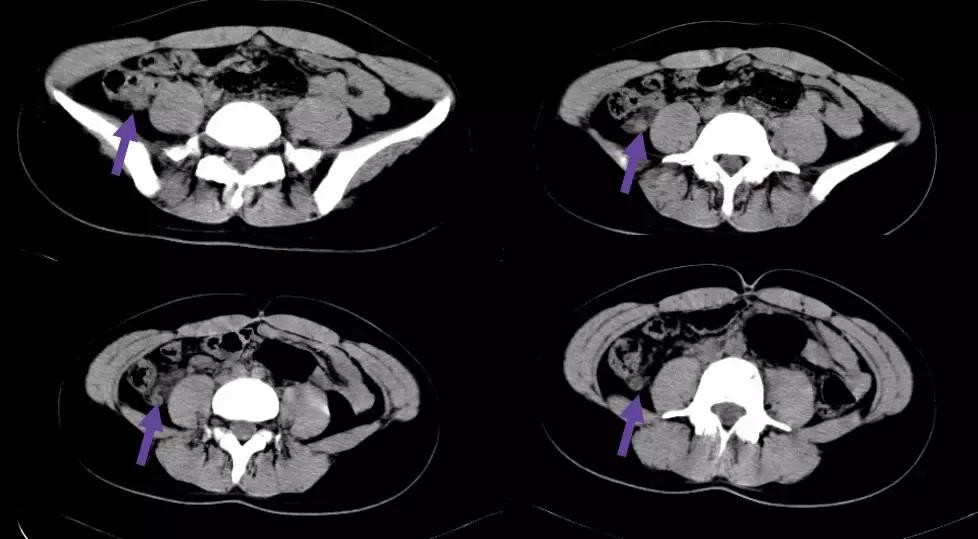

1. 回肠前位:尖端指向左上方

2. 盆位:尖端指向盆腔

3. 盲肠下位:尖端指向右下方

4. 回肠后位:在回肠后位,指向脐

5. 外侧位:位于腹腔内,盲肠外侧